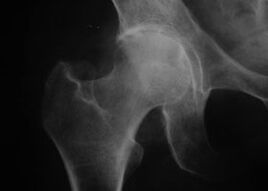

Aspecto de una articulación con artrosis

Coxatrosis, artrosis de la articulación de la cadera.

Con esta enfermedad se observa un cuadro clínico clásico de osteoartritis.

El primer síntoma de la coxartrosis es el malestar en la articulación de la cadera después de la actividad física.

A medida que avanza la coxartrosis, aumenta el dolor, se produce rigidez y movilidad limitada.

Los pacientes con una forma grave de coxartrosis protegen la extremidad afectada, evitan pisarla y, cuando están quietos, eligen posiciones en las que el dolor sea menos perceptible.